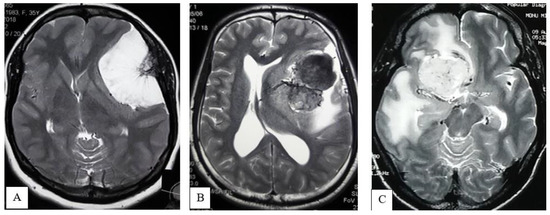

- Extrapial: Surgical cleavage plane lies outside the pia mater in more than two-thirds of the overall interface between tumor and cortex, regardless of whether an arachnoid membrane could be clearly identified (Figure 4A);

- Mixed: Cleavage plane lies outside the pia mater in more than one-third but less than two-thirds of overall interface (Figure 4B);

- Subpial: Tumor capsule exceeds the pia mater in more than two-thirds of the tumor cortex interface, and the surgeon was required to pass underneath the pia mater because of its incorporation into the tumor capsule (Figure 4C).